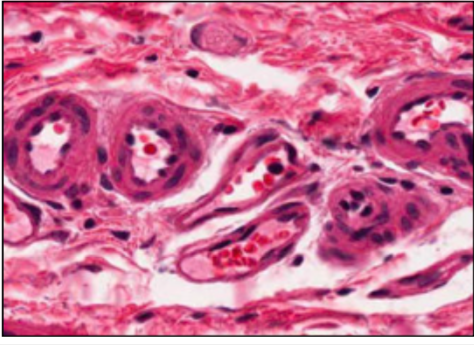

CAPILLARIES

- sometimes have contractile pericytes along bed

- continuous or fenestrated (gut, kidney glomerulus, endocrine glands)

- diameter is size of RBC

this slide - mature adipose